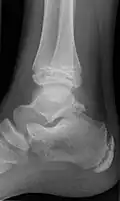

Ankle

Accessory bones at the ankle mainly include:

- Os subtibiale, with a prevalence of approximately 1%.[14] It is a secondary ossification center of the distal tibia that appears during the first year of life, and which in most people fuses with the shaft at approximately 15 years in females and approximately 17 years in males.[14]

- Os subfibulare, with a prevalence of approximately 0.2%.[15]

Os trigonum (further described below) may also be seen on an ankle X-ray.